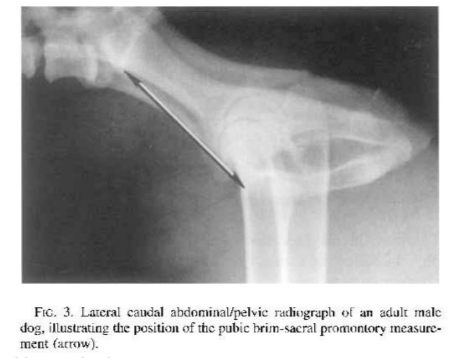

What are considered normal measurements of the prostate on radiographs?

Lateral view: < 70% of the height of the pubic-sacral promontory

VD view: <50% of the pelvic inlet width